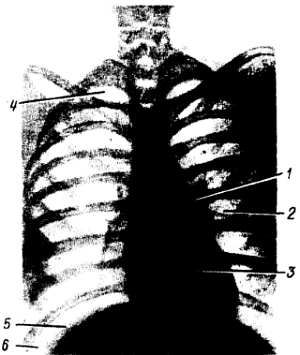

Рис. 162.Рентгенограмма грудной клетки.

1 - тень гилюса; 2 - легочный рисунок; 3 - срединная тень сердца и крупных сосудов; 4 - область верхушки легкого; 5 - диафрагма; 6 - плевральный синус.

Собственно легочная ткань видна в светлых ромбовидных промежутках между ребрами. В этих местах заметен сетевидный или пятнистый рисунок, состоящий из более или менее узких тяжеобразных теней, наиболее интенсивных в области ворот легких и постепенно убывающих по интенсивности от срединной тени сердца к периферии легочных полей. Это так называемый легочный рисунок. По обе стороны тени сердца на протяжении передних частей II–V ребер располагаются своеобразные интенсивные тени корней легких - так называемые тени hílus, или корневые тени. От тени сердца они отделены небольшой светлой полоской главных бронхов. Тень левого корня несколько короче и ýже, так как она больше прикрывается тенью сердца, чем справа.

Анатомической основой тени hílus и легочного рисунка являются сосуды малого круга кровообращения - легочные артерии и вены с радиарно отходящими от них ветвями, рассыпающимися в свою очередь на мелкие веточки. (Лимфатические узлы в норме не дают тени; они делаются видимыми только при увеличении или обызвествлении патологического характера.)